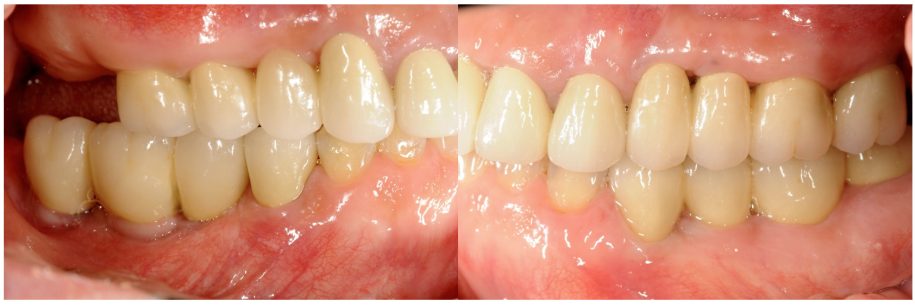

歯周病に罹患した患者さんのインプラント治療の症例②(うえだ歯科)

上田大介(うえだ歯科)

症例詳細

| 主訴 | 全顎治療希望、全顎的に歯が動く、奥の歯がなくて噛めない。できるだけ綺麗で噛めるようになりたい。 |

| 治療内容 | 全顎的に歯周病、前歯部の被蓋が深く、重度歯列不正が認められるため、 歯周外科を含む歯周治療、矯正治療、インプラント治療、セラミックによる補綴治療後メインテナンスに移行しました。 |

| 治療費 | 5,060,000円(税込)(インプラントすべて含む) |

| 治療期間 | 2年4ヶ月 |

| 治療回数 | 90回 |

| 想定されたリスク | 矯正治療の後戻り、歯周病の再発、食いしばり(パラファンクション)によるセラミックの破折、歯の破折のリスクがありました。 |